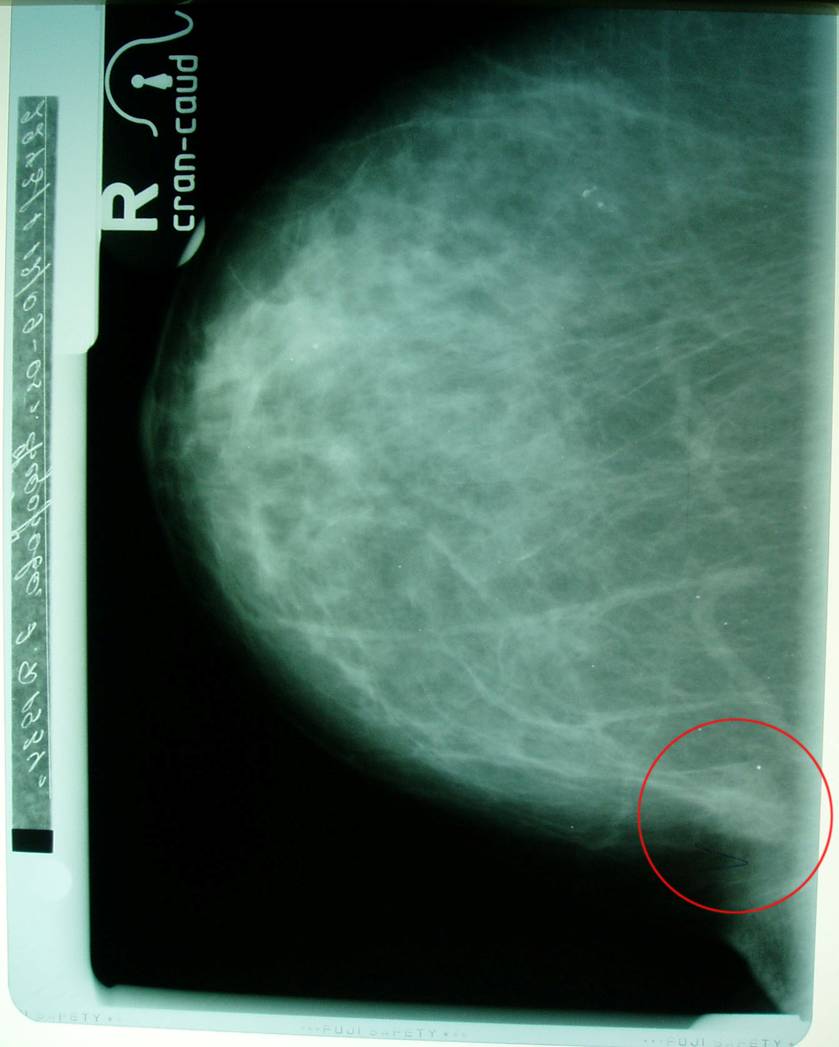

Маммограмма в динамике.

Больная раком правой молочной железы T4аN0M0. Регресс.

06.06.2005 (на момент выявления болезни)